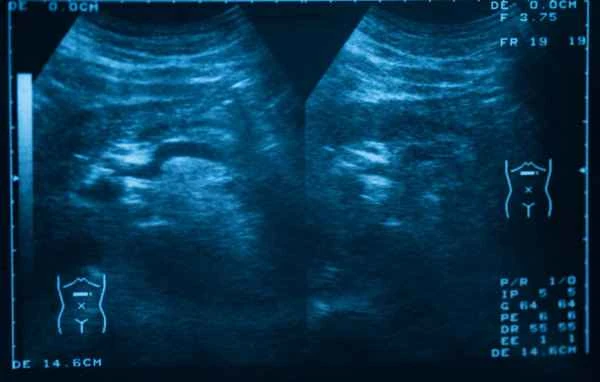

Color Doppler ultrasound uses sound wave reflection to generate images, allowing doctors to observe intestinal motility, the degree of intestinal dilation, and whether there is any obstruction. This procedure is non-invasive and relatively safe and comfortable for young children. During the examination, doctors will use features in the ultrasound images to determine if there is intestinal obstruction, such as abnormal gas distribution in the intestines or thickening of the intestinal wall.

The interpretation of examination results requires a professional doctor, who will determine the degree and type of intestinal obstruction based on the specific details of the ultrasound images. Parents should remain calm and objectively view the examination results. They should also recognize that while ultrasound is an effective diagnostic tool, it has limitations and cannot cover all possible situations. After undergoing an ultrasound examination, parents should follow the doctor's advice and promptly seek necessary treatment and observation.